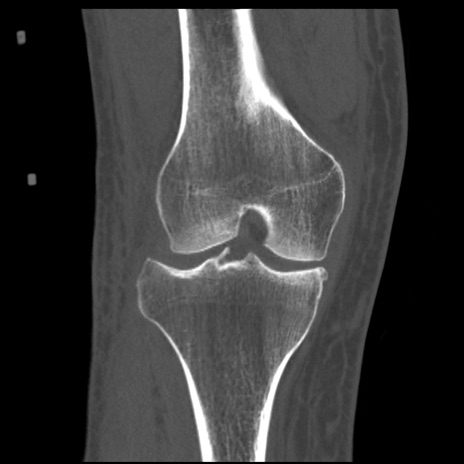

症例28 右膝関節CT(冠状断像)

右膝関節CT